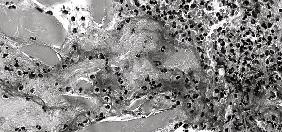

epithelial glandular neoplasm invading the surrounding fibrous connective tissue. The neoplasm demonstrated two growth patterns: solid aggregates of neoplastic cells exhibiting tumor cell necrosis (comedo necrosis) and neoplastic cells arranged in a cribriform pattern (Figures 3 and 4). Scattered small ducts with tiny lumina were noted in the solid areas. In the cribriform areas, cystic and pseudocystic spaces were evident, some of which contained a central basophilic material. A homogenous eosinophilic material, consistent with basal lamina, was noted surrounding some of the cribriform islands. The individual tumor cells contained round to oval shaped lightly basophilic nuclei with prominent nucleoli and pale eosinophilic cytoplasm. Scattered mitotic figures were noted in the neoplastic cells. Although extensive sampling was performed, no perineural invasion was identified. The neoplastic cells transected all surgical margins. Additional immunohistochemical stains were performed for phenotypic analysis and to rule out other malignant glandular neoplasms.

Figure 3. Malignant glandular neoplasm exhibiting solid islands of tumor cells and focal cystic areas (center and lower right) (H&E: original magnification 4x).

Figure 4. Malignant glandular neoplasm exhibiting a focal cribriform pattern (center), cystic and pseudocystic spaces, and solid islands of neoplastic cells (far right)(H&E: original magnification 10x).